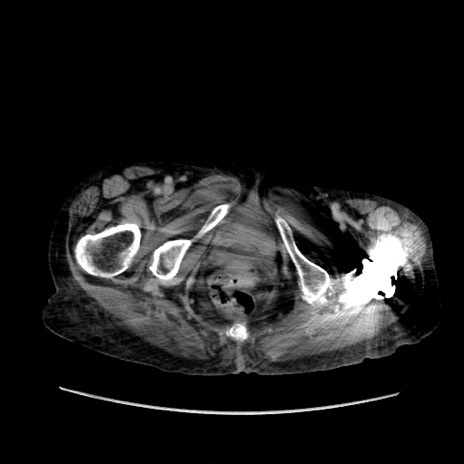

症例31(横断像)

【症例】80歳代 女性

【主訴】腹部膨満感

【現病歴】他院にて肝硬変にてフォロー中。1週間前から便秘、腹部膨満感、臍部腫瘤あり受診となる。

【既往歴】肝硬変

【身体所見】腹部膨隆あり、皮膚変化なし、疼痛なし。

【データ】WBC 4600、CRP 0.25